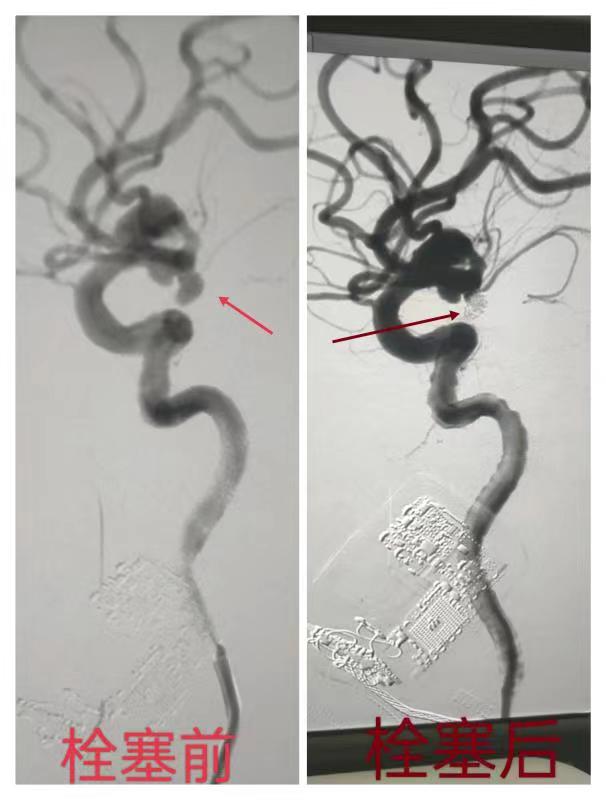

随着麻醉医生完成气管插管置,患者生命体征逐渐稳定,医护团队开始施行介入下脑动脉瘤的弹簧圈栓塞术。“血管弯曲多、角度大,导丝不好到位”,“回撤导丝,换个角度旋转一下。稳住导丝、导管跟上…..”,手术医生目不转睛地盯着显示屏,手里精准操作,技师根据要求,随时更新显示屏上的影像图片,配台护士,密切观察患者的生命体征。所有人分工明确、各司其职,导管室里安静的只剩下监护仪发出的清脆、有节奏的滴答声。随着5枚弹簧圈精准地填塞在动脉瘤的瘤腔内,造影显示:动脉瘤栓塞成功了!大家都替大娘由衷地感到高兴,铅衣的厚重、刷手衣裤上的斑斑汗渍,在此时都显得格外有意义。